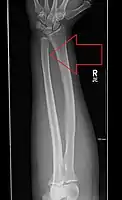

Front view of bowing fractured radius and ulna

Side view of bowing fractured radius and ulna